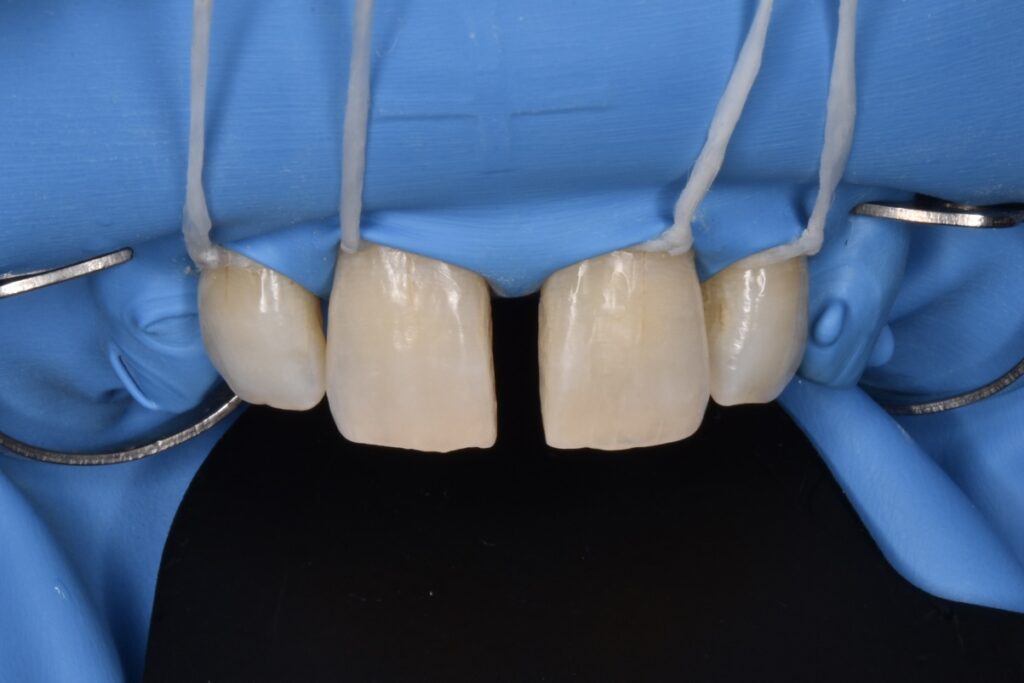

施術中

ダイレクトボンディングの治療は必ずラバーダム防湿を行います。局所麻酔をして行うため痛みはありません。

*他院で行われたダイレクトボンディングの除去はかなり大変です。除去費用として1歯税別5000円頂いております。歯を削らずマイクロスコープを使用して丁寧に除去するためです。